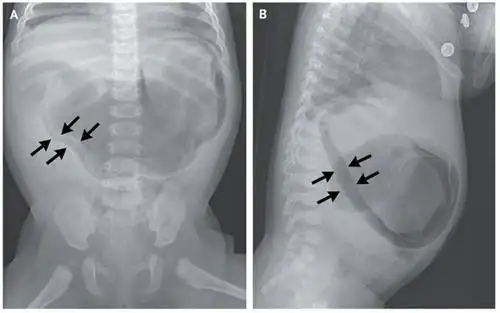

气腹征